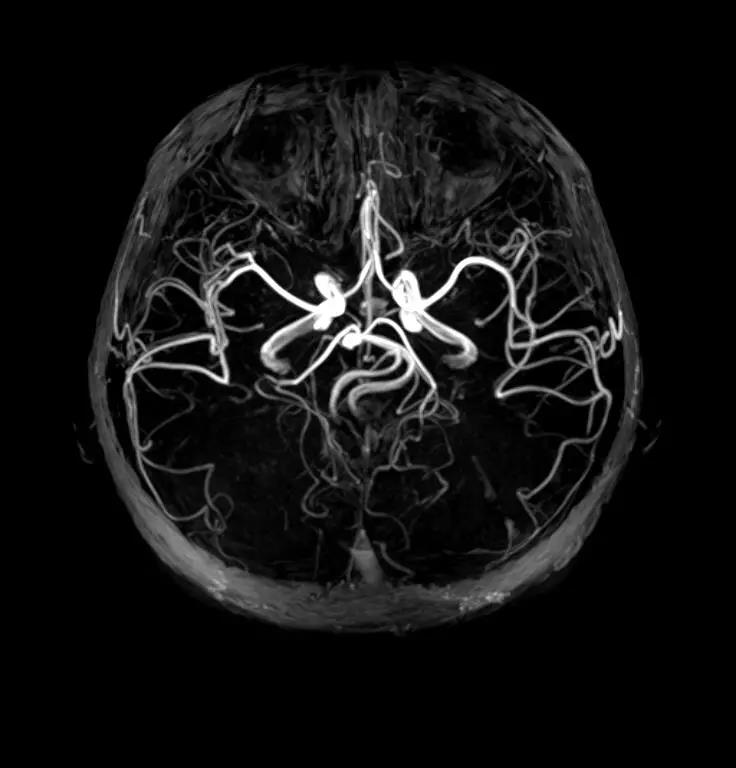

10 脑血管清晰显示